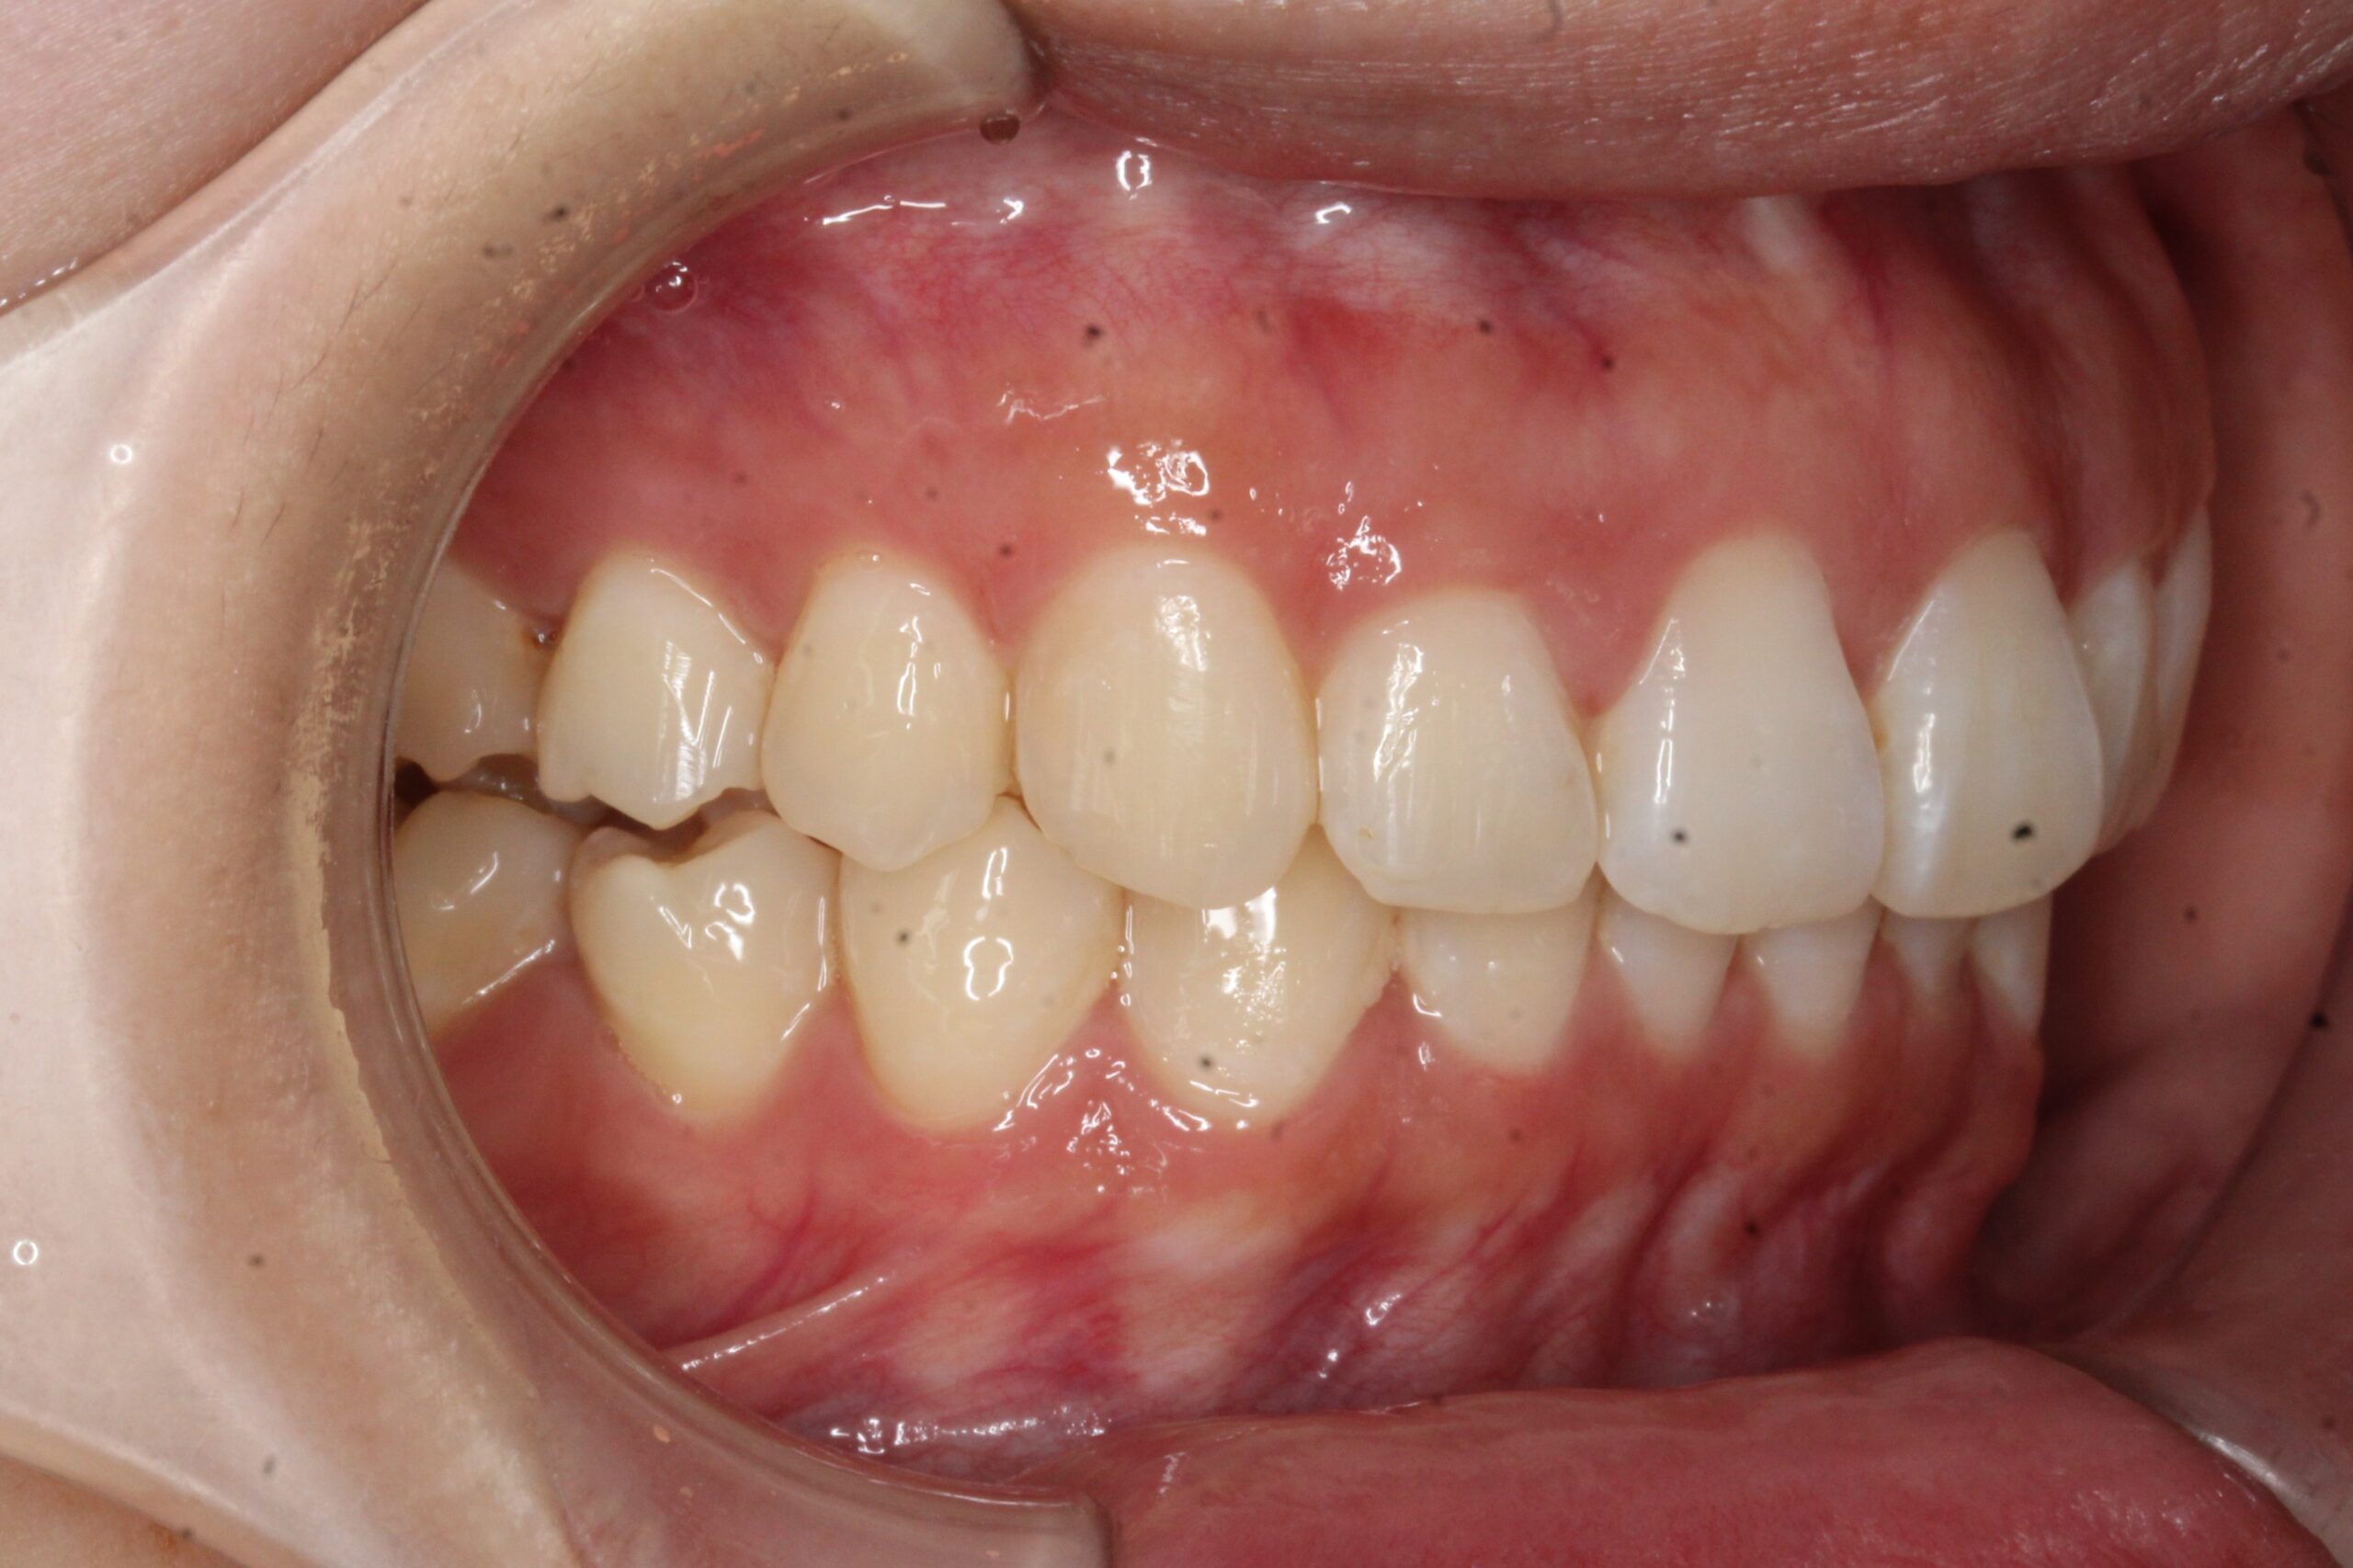

矯正術前:左側

矯正術後:左側